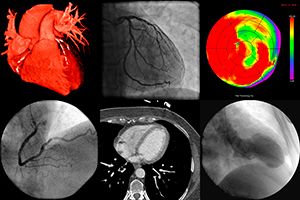

El SPECT cardíaco es una prueba de radiodiagnóstico en la cual se combinan imágenes (obtenidas en una gammacámara) y la administración de radiofármacos (MBI o Talio).

Esta prueba permite estudiar con precisión el comportamiento del músculo cardiaco (miocardio) durante el ejercicio y en reposo, y así valorar el aporte de sangre en ambas situaciones. Con el estudio del flujo sanguíneo miocárdico se pueden valorar la existencia de obstrucciones en las arterias coronarias así como la permeabilidad de los stent o bypass colocados previamente.

El SPECT cardíaco es especialmente útil para valorar el grado de irrigación (perfusión) del músculo cardíaco durante el reposo y cuando se realiza ejercicio, sobre todo en aquellos casos en los que otras pruebas dan resultados dudosos.

Actualmente es una exploración más utilizada, pues permite la valoración simultánea de la perfusión miocárdica y la función ventricular, tanto en condiciones de reposo como su respuesta al esfuerzo, aportando información de gran interés diagnóstico y también pronóstico.